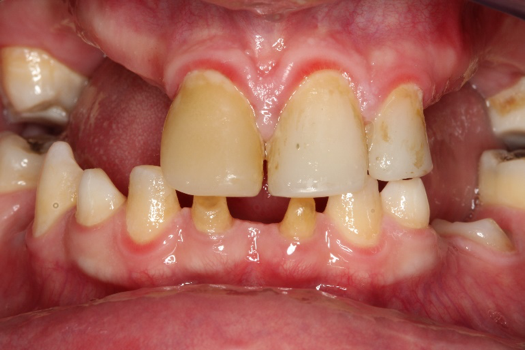

Fig 8. Photograph, 14-year-old brother.

Figure 8

Figure 5 through Figure 12 exemplify what currently may present in private dental practices with these types of patients. Four brothers aged 14 years to 27 years all suffered from obstructed airways; high incidence of caries of dentin, enamel, and cementum; moderate periodontal disease; collapsed vertical; undiagnosed OSA; and the potential for increase in comorbidities such as diabetes, cardiovascular disease, dementia, cancer, high blood pressure, and others. Symptomology was presented throughout the young lives of the brothers in this family. The parents were unaware that the dental agenesis and premature permanent tooth extraction could have led their sons into severe health issues as they matured.

Swift intervention took place with caries control, periodontal care, orthodontic evaluation for arch form development to aid in the development of facial bones and creating an improved upper airway with nasal patency. These interventions were followed up with definitive implant therapies and rapidly advancing restorative technology and materials. Thus, not only were these young men's smiles restored, they also were provided with the opportunity to regain their dignity when they become confident with their new smiles.